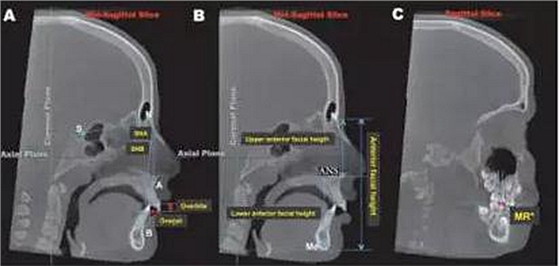

圖1:3D參考平面的的定為:軸面:通過左右眶下點(diǎn)及右側(cè)耳點(diǎn)的平面;冠狀面,通過左右耳點(diǎn)并垂直于軸面的平面;矢狀面,通過鼻根點(diǎn)并垂直于軸面及冠狀面的平面。

圖2:矢狀面上標(biāo)志點(diǎn)的測量:A,SNA, SNB, 覆合覆蓋的測量;B,上前面高N-ANS,下前面高ANS-Me的測量;C,左右磨牙關(guān)系的測量:上頜第一磨牙近中頰尖與下頜第一磨牙近中頰溝的水平距離,但在擴(kuò)弓完成的即刻(T2)因?yàn)槟パ缼Лh(huán)的阻擋,該數(shù)據(jù)無法測量。